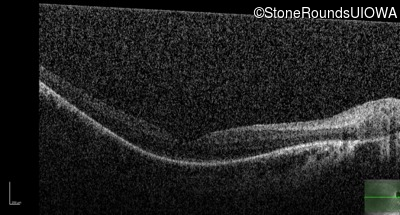

Optical Coherence Tomography - Right - 20/70 -2

Exemplar / OCT Stack